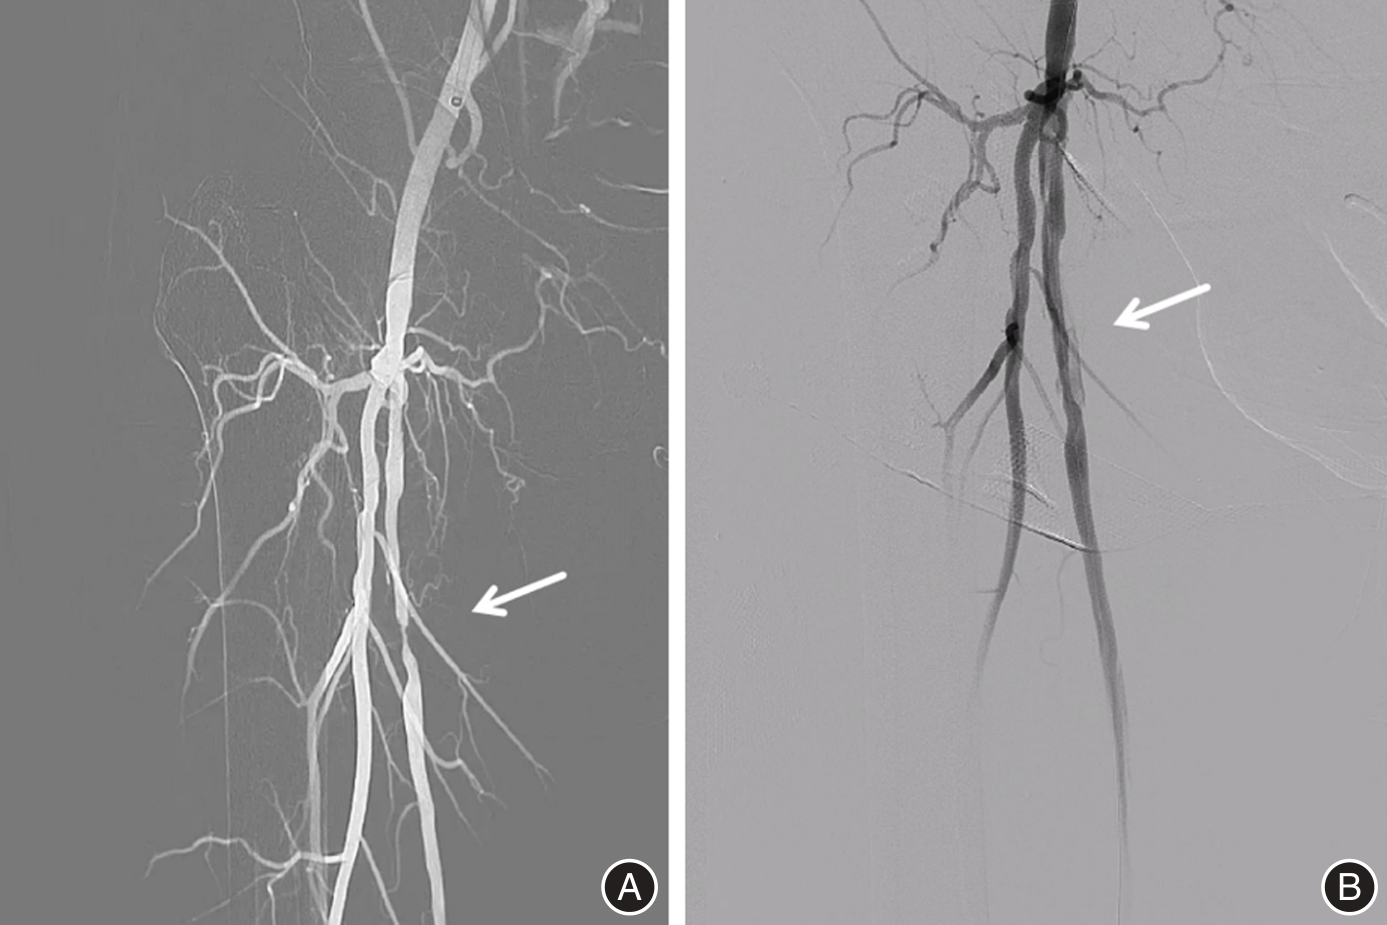

目的 探讨置管溶栓结合多种腔内介入术在改善下肢动脉硬化闭塞症患者动脉硬化指标中的应用。 方法 采用随机数字表法将2021年12月至2024年12月医院收治的下肢动脉硬化闭塞症患者125例分为对照组(63例,失访3例,最终60例)、观察组(62例,失访2例,最终60例)。对照组予以腔内介入治疗,观察组予以置管溶栓后行腔内介入治疗,两组均随访至介入治疗后6个月。比较两组临床疗效(治疗后6个月),行走受损问卷(WIQ)评分、Berg平衡量表(BBS)、视觉模拟评分(VAS)、Rutherford分级、血流动力学指标、动脉硬化指标、下肢神经传导速度、血清学指标(治疗前、治疗后6个月),并发症发生情况(随访期间)。 结果 治疗后6个月,观察组临床总有效率(93.33%)高于对照组(78.33%)(P < 0.05)。治疗后6个月较治疗前,两组行走距离、步行速度、爬梯能力评分均升高,观察组更高(P < 0.05)。治疗后6个月较治疗前,两组BBS评分均升高,观察组更高,VAS评分、Rutherford分级 > 3级的患者占比则均降低,观察组更低(P < 0.05)。治疗后6个月较治疗前,两组动脉血管内径均增厚,观察组更厚,血流量则均增加,观察组更多,血流峰速则加快,观察组更快,踝肱指数(ABI)则升高,观察组更高(P < 0.05)。治疗后6个月较治疗前,两组颈动脉内中膜厚度(IMT)均减小,观察组更小,脉搏波传导速度(PWV)则均减慢,观察组更慢,运动、感觉神经传导速度则加快,观察组更快(P < 0.05)。治疗后6个月较治疗前,两组血清血管内皮生长因子(VEGF)水平均升高,观察组更高,血清内皮素-1(ET-1)、超敏C反应蛋白(hs-CRP)、肿瘤坏死因子α(TNF-α)水平则均降低,观察组更低(P < 0.05)。随访期间,观察组并发症总发生率(3.33%)低于对照组(15.00%)(P < 0.05)。 结论 置管溶栓后行腔内介入治疗可稳定下肢动脉硬化闭塞症患者血流动力学指标,调整其动脉硬化指标,加快下肢神经传导速度,改善患者血管内皮功能,降低机体炎性因子水平,提高患者行走能力、运动功能,减轻患者疼痛感及下肢动脉缺血程度,疗效显著且能降低并发症发生率。

Objective To investigate the application of catheter-directed thrombolysis combined with various endovascular interventions in improving arteriosclerotic indices in patients with lower limb arteriosclerosis obliterans. Methods A total of 125 patients with lower limb arteriosclerosis obliterans admitted to the hospital between December 2021 and December 2024 were randomly assigned, using a random number table method, into a control group (n = 63, with 3 lost to follow-up, resulting in 60 evaluable cases) and an observation group (n = 62, with 2 lost to follow-up, resulting in 60 evaluable cases). The control group received endovascular interventional therapy alone, whereas the observation group underwent catheter-directed thrombolysis prior to the same endovascular intervention. Both groups were followed up for 6 months post-intervention. Outcomes assessed included clinical efficacy at 6 months after treatment, Walking Impairment Questionnaire (WIQ) scores, Berg Balance Scale (BBS) scores, Visual Analogue Scale (VAS) scores, Rutherford classification, hemodynamic indices, arteriosclerosis index, nerve conduction velocity in the lower limbs, serological markers (measured before treatment and 6 months post-treatment), and incidence of complications during follow-up. These outcomes were compared between the two groups. Results Six months after treatment, the total clinical effective rate in the observation group (93.33%) was significantly higher than that in the control group (78.33%) (P < 0.05). Compared with pre-treatment levels, both groups showed improvements in walking distance, walking speed, and stair-climbing ability, with greater gains observed in the observation group (P < 0.05). The Berg Balance Scale (BBS) scores increased in both groups, with a more pronounced improvement in the observation group (P < 0.05). Additionally, the proportion of patients with Visual Analog Scale (VAS) scores and Rutherford classification exceeding grade 3 decreased, with a lower proportion in the observation group (P < 0.05). The arterial lumen diameter increased in both groups, while blood flow volume and peak velocity improved more significantly in the observation group, along with a greater increase in ankle-brachial index (ABI) (P < 0.05). Carotid intima-media thickness (IMT) decreased in both groups, with a greater reduction in the observation group; pulse wave velocity (PWV) slowed, and both motor and sensory nerve conduction velocities increased, with more favorable changes in the observation group (P < 0.05). Serum levels of vascular endothelial growth factor (VEGF) increased in both groups, particularly in the observation group, while levels of endothelin-1 (ET-1), high-sensitivity C-reactive protein (hs-CRP), and tumor necrosis factor-α (TNF-α) decreased, with more marked reductions in the observation group (P < 0.05). During the follow-up period, the overall complication rate in the observation group (3.33%) was significantly lower than that in the control group (15.00%) (P < 0.05). Conclusions Endovascular interventional therapy following catheter-directed thrombolysis can stabilize hemodynamic parameters in patients with lower limb arteriosclerosis obliterans, modulate atherosclerotic markers, accelerate lower limb nerve conduction velocity, improve vascular endothelial function, reduce systemic inflammatory factor levels, enhance walking capacity and motor function, alleviate patient pain, and mitigate the degree of lower limb arterial ischemia. This combined approach demonstrates significant therapeutic efficacy and reduces the incidence of complications.